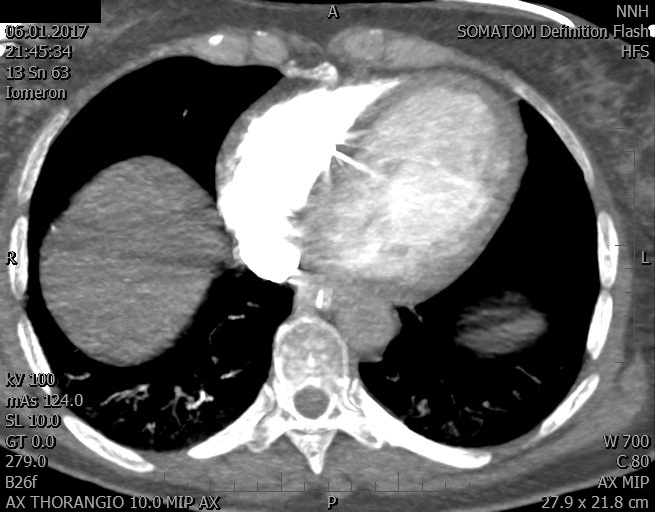

Video 2 - Echokardiograficky byla zjištěna těžká dysfunkce dilatační levé komory s nezvětšenou pravou komorou.Pro nejasnou příčinu zástavy jsme provedli i vyšetření výpočetní tomografií (CT), které vyloučilo plicní embolizaci (série 1 - soubory na konci článku). V den přijetí při přetrvávající oběhové nestabilitě byla nemocná opakovaně defibrilována pro fibrilaci komor se stabilizací rytmu po podání amiodaronu a mesocainu. Dle hemodynamických měření se jednalo o těžký kombinovaný šok. Vstupní laboratorní vyšetření bylo bez větších pozoruhodností. Posléze jsme doplnili anamnézu od příbuzných a zjistili, že pacientka užila do dvou hodin před srdeční zástavou první tabletu amoxicilinu na lehký respirační infekt. Při nevýtěžnosti vstupních vyšetření a nových anamnestických informacích jsme doplnili 14 hodin po kolapsu vyšetření koncentrace tryptázy v séru, která byla extrémně zvýšena (tabulka 2), což nás vedlo k podezření na anafylaxi.